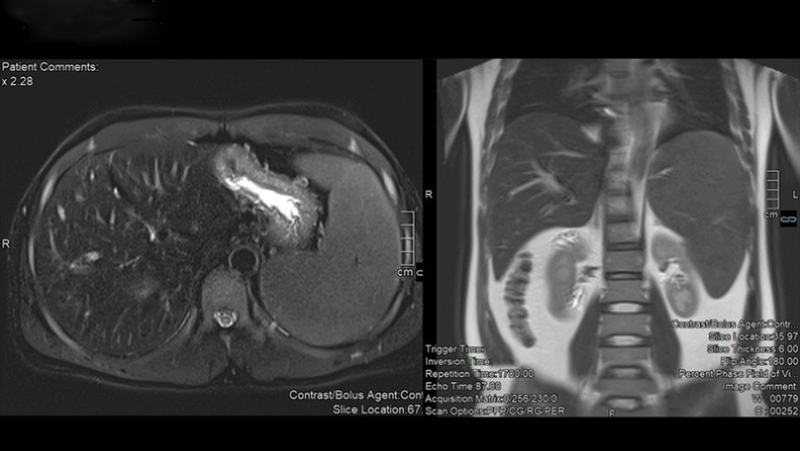

Trong những trường hợp nghiêm trọng nhất, tình trạng quá tải sắt trong gan có thể dẫn đến ung thư gan. Đây là một biến chứng đặc biệt nguy hiểm, thường đòi hỏi phải điều trị tích cực và chuyên sâu. Ung thư gan phát sinh do quá tải sắt là một tình trạng nghiêm trọng có ý nghĩa quan trọng đối với sức khỏe và tiên lượng của bệnh nhân.